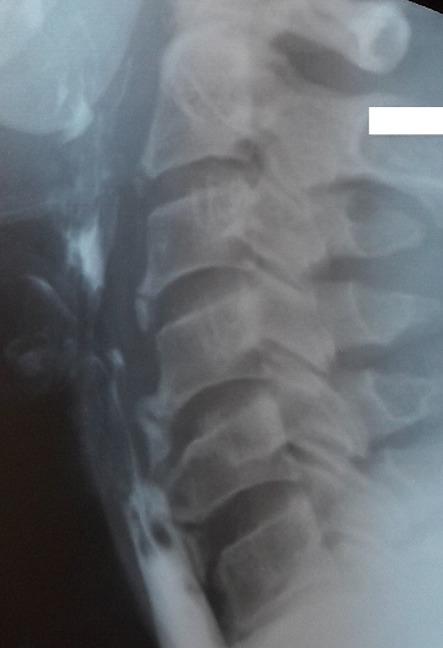

Diffuse Idiopathic Skeletal Hyperostosis (DISH) also known as Forestier's disease, is a musculoskeletal disorder characterized by the calcification of ligaments essentially the vertebral longitudinal anterior ligament. Men are generally affected. It is often asymptomatic. The most common extra-spinal clinical manifestation of this disease presents as dysphagia followed by respiratory disturbances such as dyspnea and sleep apnea. In this paper we discuss two cases where the patients have experienced progressive dysphagia. Radiological findings were compatible with DISH. The management was based on diet modification and anti-inflammatory medication.

弥漫性特发性骨肥厚(DISH),也称为福里斯特尔病,是一种肌肉骨骼疾病,其特征是韧带钙化,主要是椎体前纵韧带钙化。男性通常易患此病。该病常无症状。这种疾病最常见的脊柱外临床表现是吞咽困难,其次是呼吸障碍,如呼吸困难和睡眠呼吸暂停。在本文中,我们讨论了两例患者出现进行性吞咽困难的病例。影像学检查结果与DISH相符。治疗方法是调整饮食和使用抗炎药物。